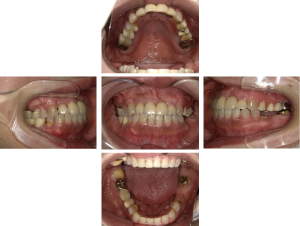

インプラント治療(左上5ソケット・GBR 右上2左上13GBR)

| 年代・性別 | 50代・男性 |

|---|---|

| 主訴 | 入れ歯だと咬めなくてつらい。 |

| 部位 | 上顎②1①2③4⑤Br |

| 治療期間 | 約9ヶ月 |

| 費用 | ¥1,794,100(税込) |

| 副作用・リスク |

|